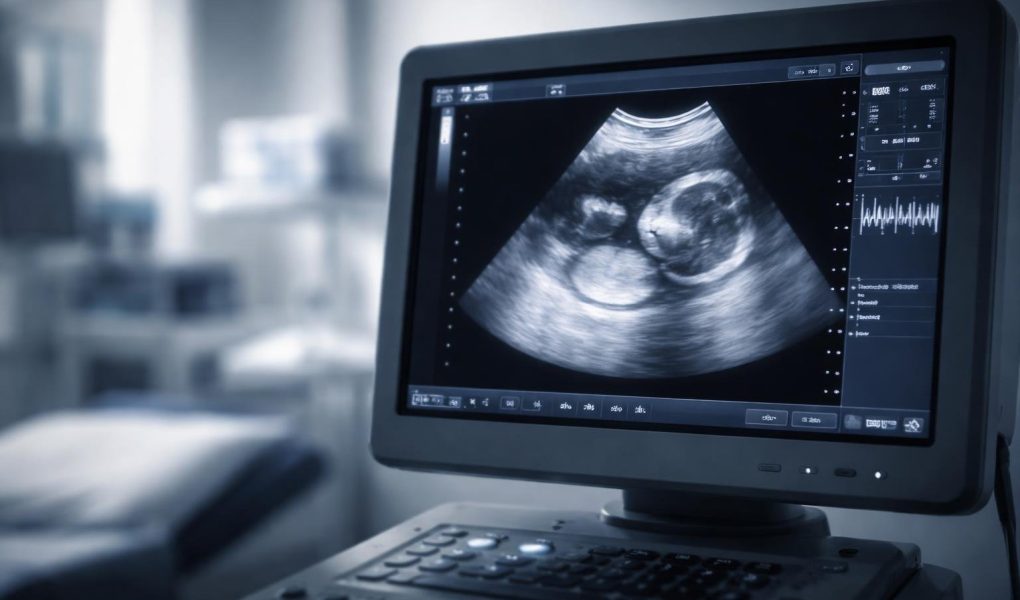

L’échographie à 9 SA (semaines d’aménorrhée) est un moment charnière où l’embryon commence sa mutation pour devenir un fœtus. Cet article vous explique précisément ce que le professionnel de santé va observer pour s’assurer que votre grossesse se déroule normalement.

Ce que l’on voit précisément à l’écran : L’anatomie de l’embryon

À ce stade du développement prénatal, l’aspect de l’embryon change radicalement. Il perd sa forme de « C » très courbée pour commencer à se redresser progressivement.

À cet âge, il ressemble un peu à un gros ours en gélatine. La tête est ronde et très inclinée vers l’avant. On voit bien la distinction entre le haut et le bas du corps. Les clichés en 2D montrent souvent une forme blanche sur fond noir, entourée d’un halo clair qui est le liquide amniotique.